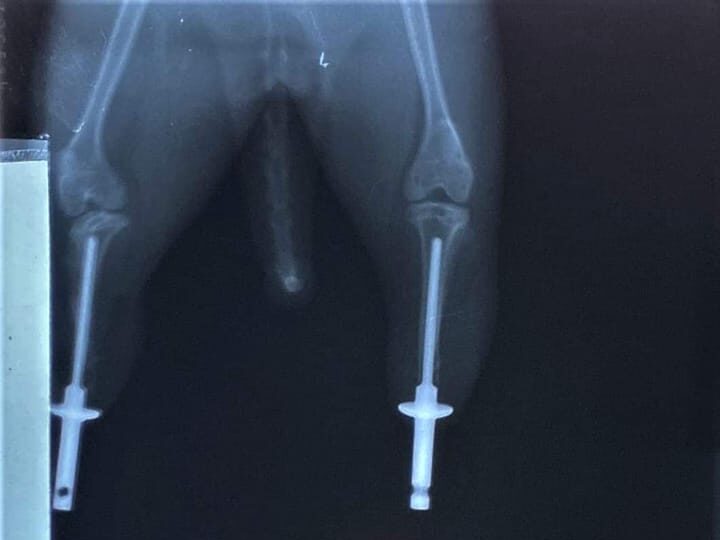

Když se konečně zadařilo a Mojito přestal měnit váhu (a to i do šířky, protože jeho adoptivní maminky ho mají veeeeeeeelmi rády), přišel na řadu rentgen a spolupráce s AnyoneGo a jejich vývojářem. Ten pomohl navrhnout 3D model nových nožiček spolu s odborným dozorem pana veterináře.

Až se jednoho dne konečně podařilo obnovit výrobu a firma vyrobila titanové nožičky pro Mojita. Následovaly opět rentgeny a kontroly. A osudná operace přišla! A dopadla skvěle, alespoň zatím to tak vypadá.

Celá operace včetně konzultací, rentgenů, kontrolních testů a dokonce dvou chirurgů při samotném zákroku vyšla na 49998,14 Kč, v ceně je zahrnutá také pooperační péče, kontroly, hospitalizace a další konzultace stavu až do úplného zahojení. Samotné protézky stály 50000,01 Kč.